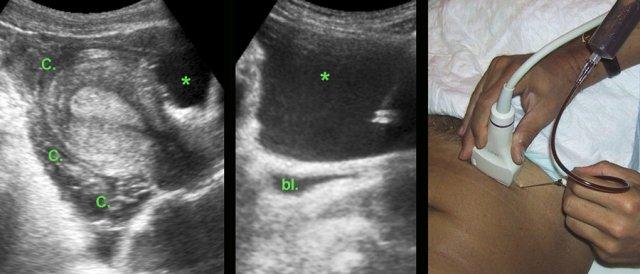

Ca lâm sàng 4

Chảy máu hoàng thể bắt chước hình ảnh thai ngoài tử cung

Ở người phụ nữ trẻ này, siêu âm cho thấy một lượng lớn máu đông (C.) và máu đã hóa lỏng (*) xung quanh tử cung, nghi ngờ thai ngoài tử cung. Tuy nhiên, nồng độ β-HCG trong cả nước tiểu và huyết thanh đều rất thấp.

Chọc hút dưới hướng dẫn siêu âm vào phần máu đã hóa lỏng xác nhận là máu. (bl. = bàng quang)

Nội soi ổ bụng phát hiện chảy máu nặng từ hoàng thể, đã được cầm máu thành công bằng đốt điện.